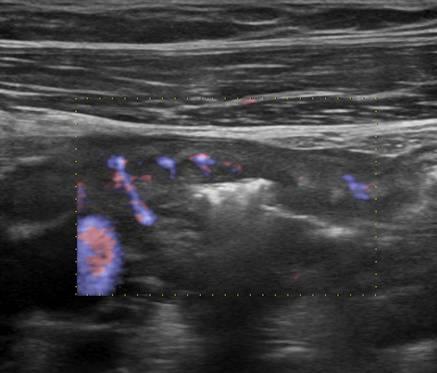

Viêm ruột

» Thông tin: Nữ giới – 18 tuổi.

» Lâm sàng: Tiêu chảy.